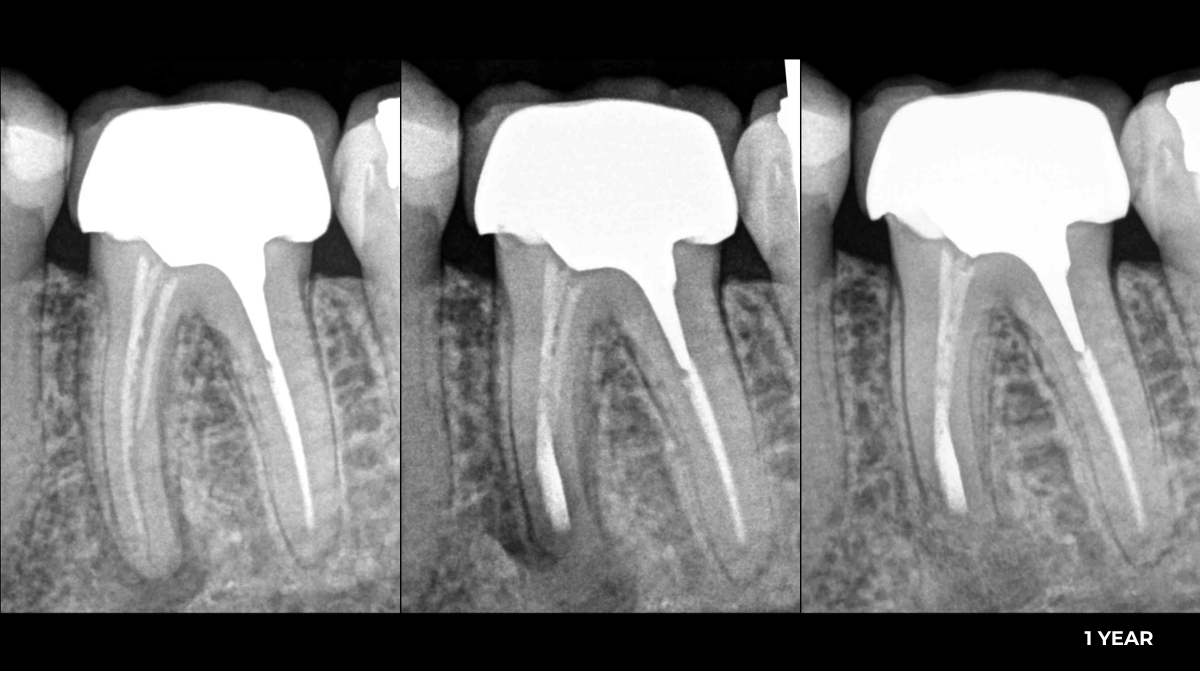

Clinical case

Clinical case